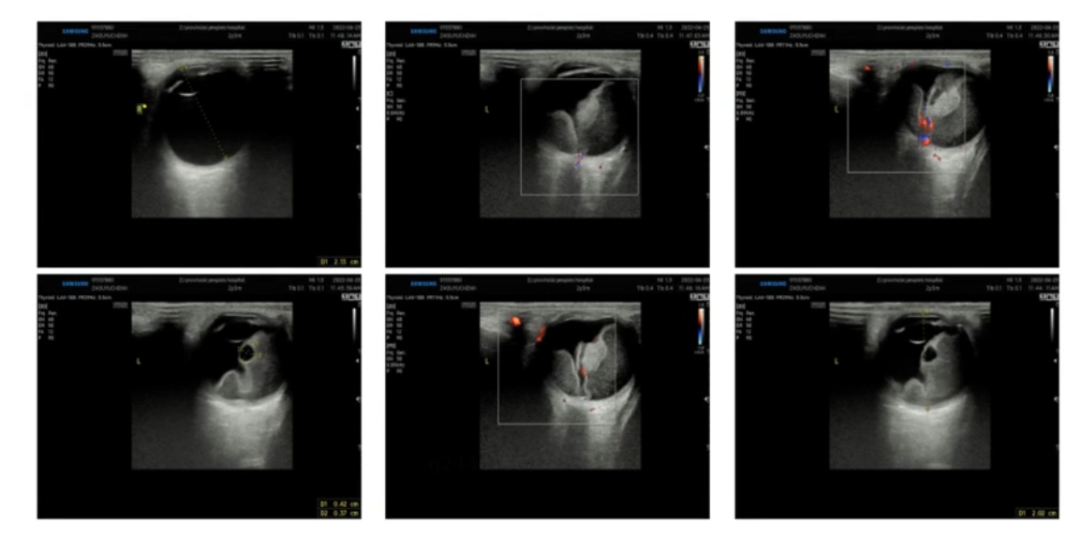

男童,2岁3个月,因体检发现左眼瞳孔呈猫眼状1个月就诊。术前B超检查可见视网膜高度脱离,巩膜外放液术中截屏可见脱离的视网膜贴近晶状体,异常血管清晰可见,背景呈黄色系视网膜下广泛的脂质渗出所致,属于Coats病3B期。本例患儿存在广泛视网膜异常血管并高度脂质性脱离,给予了巩膜外放液联合眼内光凝异常血管手术。联合抗VEGF治疗可以降低异常血管通透性并减轻炎症反应,目前临床上尚无共识,一些小样本临床研究报告首次抗VEGF治疗后6-9个月可发生纤维化甚至牵拉性视网膜脱离,但也有调查显示两者无关。本例患者光凝联合抗VEGF治疗随访2年多,渗出吸收、视网膜复位,无观察到纤维化并发症。

术前B超检查:视网膜全脱离

术中截图:眼表照明下即可看到高度隆起的视网膜及其扩张的异常血管、视网膜下脂质渗出

术后随访:视网膜基本复位,异常血管消失,少量脂质沉着